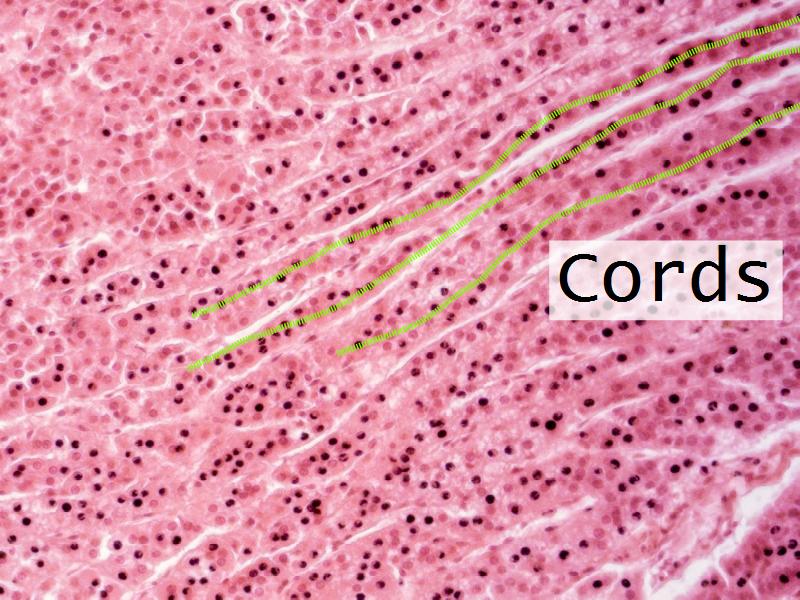

- Slide 56: Adrenal glands

Adrenal glands

Cortex - how many zones?